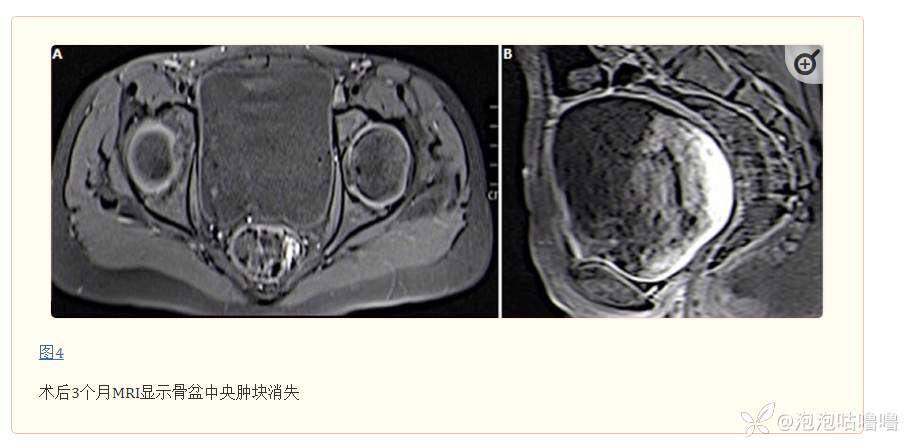

治疗:患者于手术室进行了肿块切除活检。显微镜检查显示肿瘤细胞呈网状生长模式排列,具有肾小球样结构,由中央血管组成,中央血管被具有突出核仁(席勒-杜瓦尔小体)的非典型大多形性细胞和大量细胞内和细胞外过碘酸-希夫阳性淀粉酶所包围。图2)。免疫组织化学研究表明,肿块细胞的甲胎蛋白(AFP)和细胞角蛋白(AE1/AE3)呈局灶性阳性。图3)骨骼肌标记物(结蛋白和肌细胞生成素)呈阴性,该结果通过第二次病理检查得到证实。根据组织病理学检查和免疫组化研究结果确诊了一种疾病,患者接受了 6 个疗程的依托泊苷、异环磷酰胺和顺铂治疗。新辅助化疗后的 MRI 监测显示肿瘤体积减少了 50% 以上,但随着宫颈侵犯,需要进行子宫切除术。两年的随访中没有复发的证据(图4)。